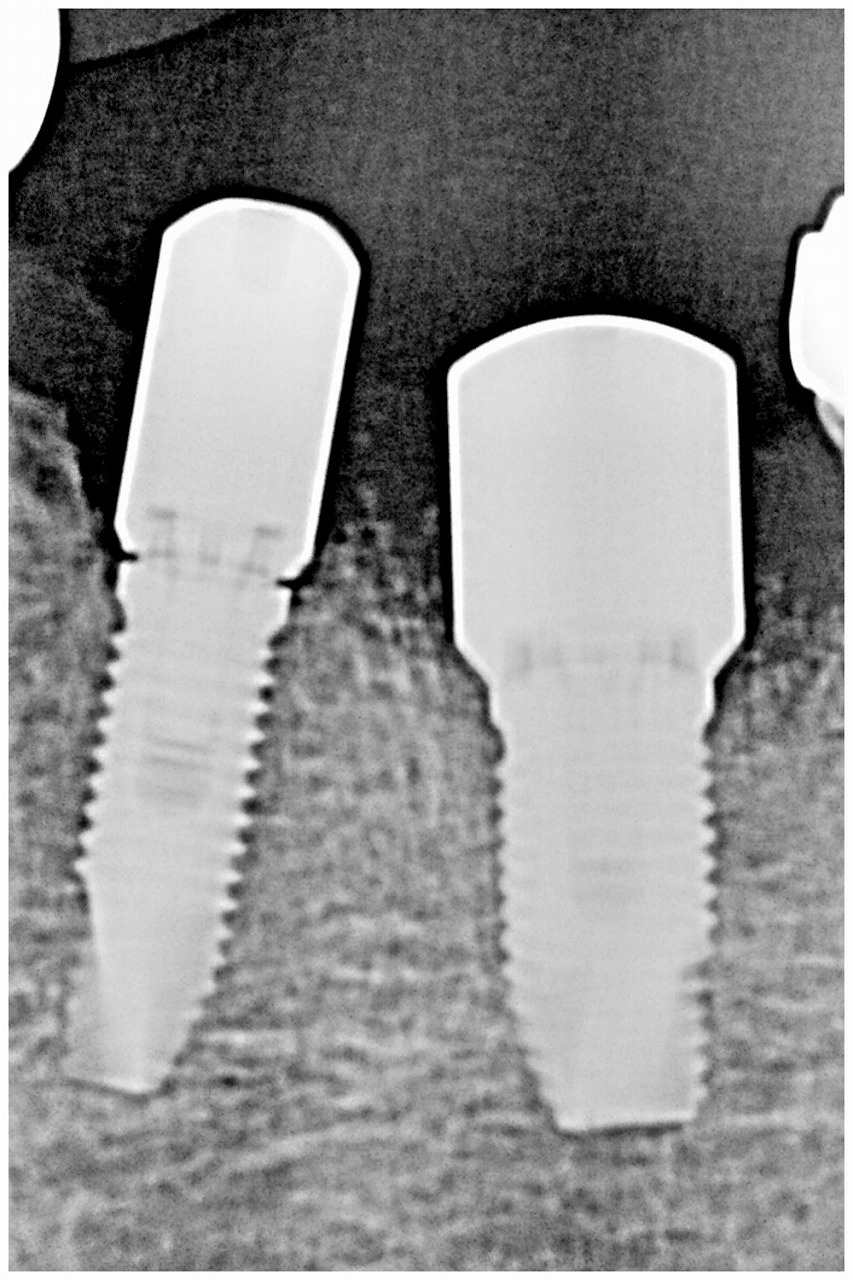

綺麗にインプラントが入りました

最終補綴になります

セラミックにて綺麗に仕上がりました